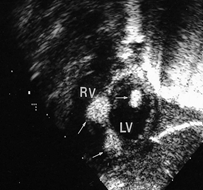

00:27 심장내과 중환자실